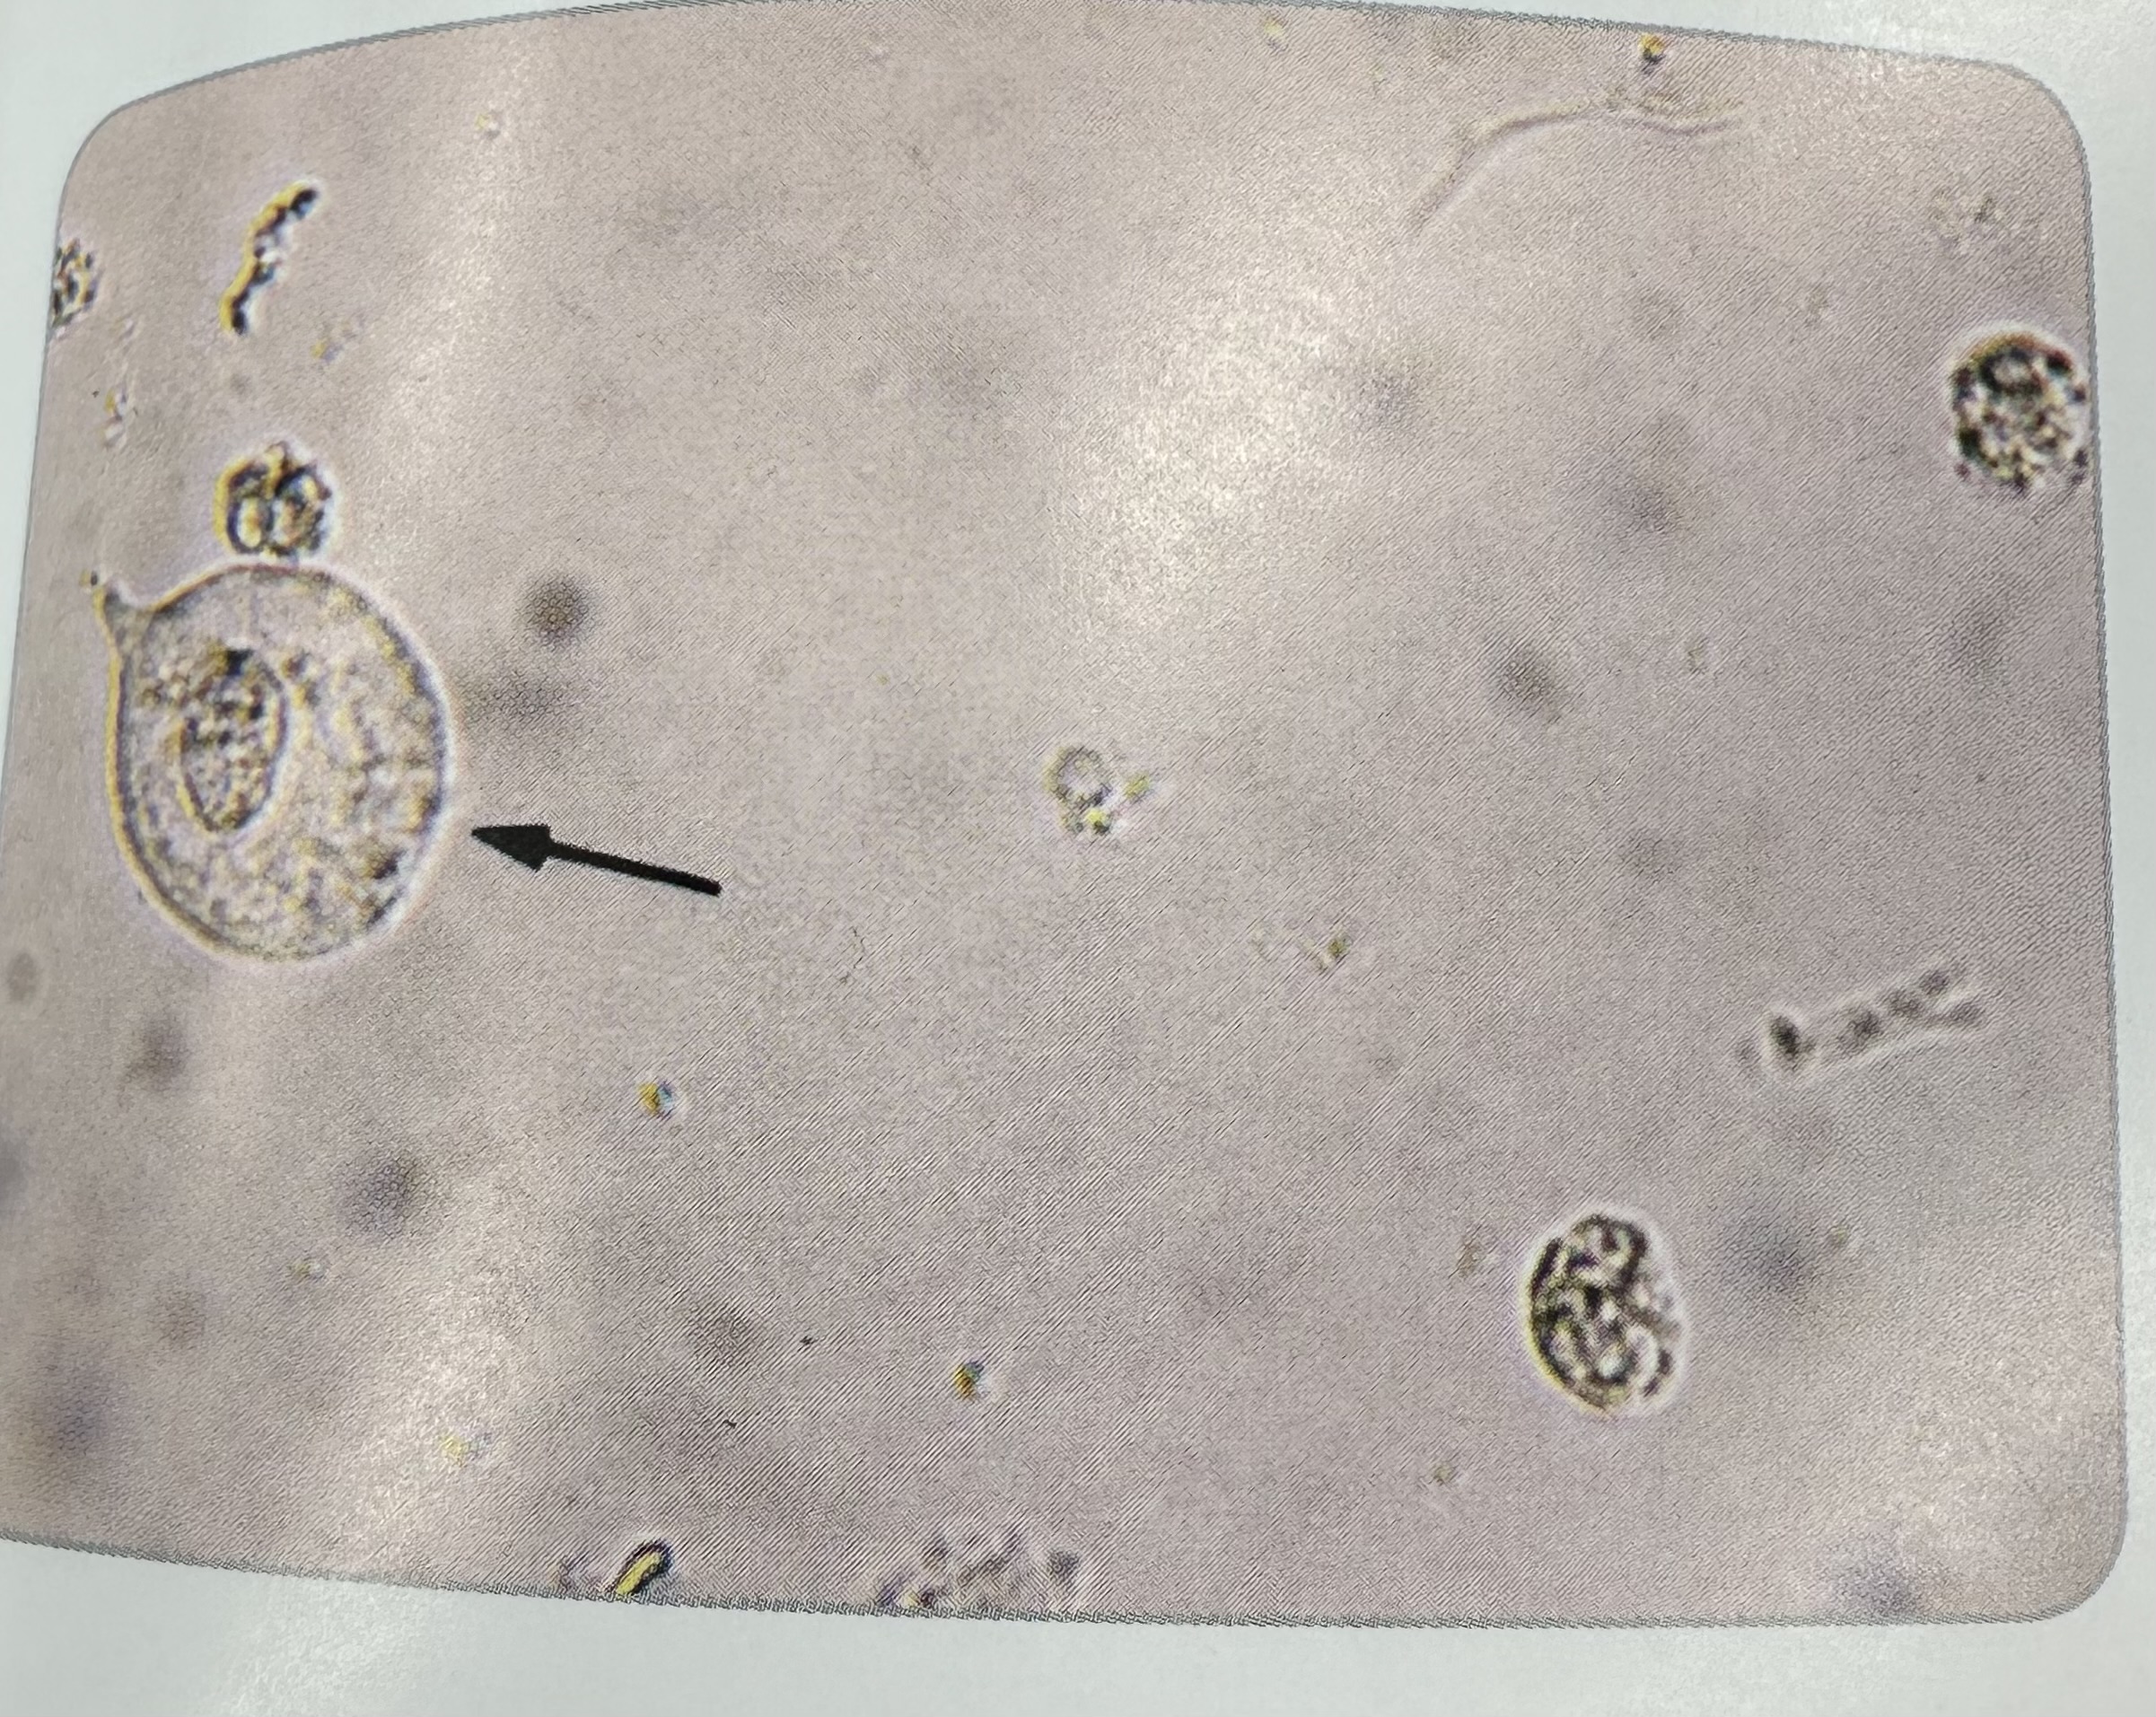

Calcium Oxalate

dihydrate forms are the octahedral envelopes

Monohydrate forms are the dumbbell or oval shapes

dihydrate forms

left is dihydrate

Right is monohydrate

different forms seen

monohydrate forms